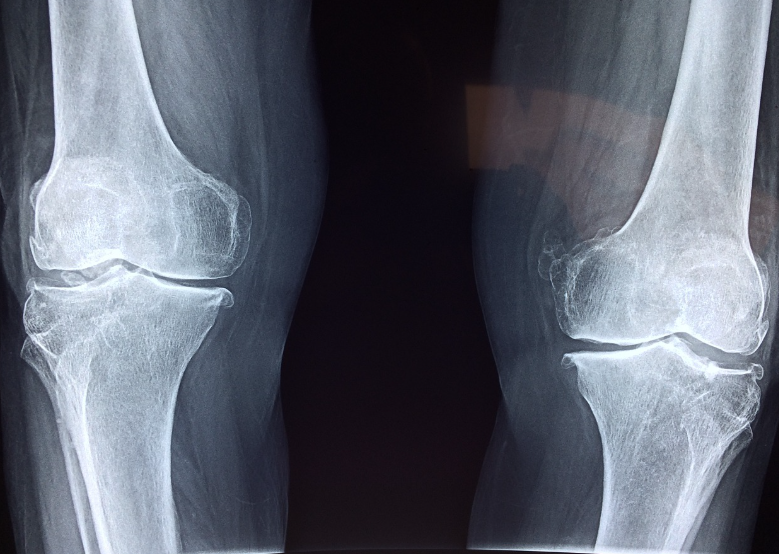

60대 여성 A씨 (퇴행성 무릎 관절염 진단)

6개월간 철갑상어 콘드로이친 복용 후, 계단 오르기나 장시간 걷기 시 통증 완화와 부기 감소를 경험함. MRI상 연골 마모 속도 감소도 확인.

70대 여성 C씨 (무릎 인공관절 수술 전 단계)

수술 연기 목적으로 철갑상어 콘드로이친 복용. 일상생활 수행능력 개선됨. 특히 아침 관절 뻣뻣함 해소가 두드러짐.